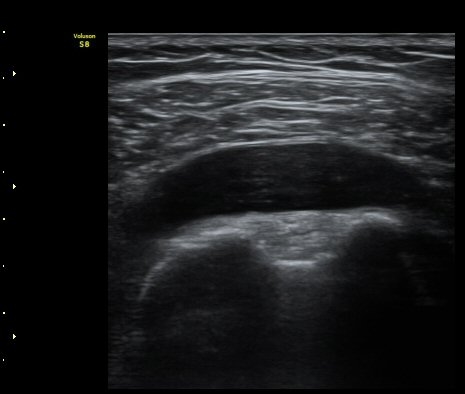

°üÀý³» ¼ö¾×Àú·ù´Â ¶Ñ·ÈÇÏÁö ¾Ê´Ù(±×¸² 3). ±Ø»ó°Ç Á¾´Ü¸é°Ë»ç¿¡¼­ Á¡¾×³¶³» ¼ö¾×

Àú·ù°¡ °üÂûµÈ´Ù(±×¸² 4, 5). ±Ø»ó°Ç Ⱦ´Ü¸é À­ ºÎºÐ¿¡¼­ °æ¹ÌÇÑ ¼ö¾×Àú·ù¸¦ º¸ÀδÙ(±×¸² 6).